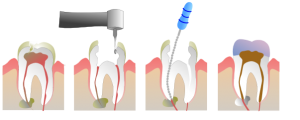

- กรอเปิดโพรงประสาท ทันตแพทย์ทำการฉีดยาชาเพื่อป้องกันและลดอาการปวด หลังจากนั้นจึงทำการเปิดโพรงประสาทฟันโดยการใช้เครื่องมือเจาะ เพื่อทำความสะอาดโพรงประสาทฟัน

- วัดความยาวและขยายโพรงประสาทฟัน เมื่อกรอเปิดโพรงประสาทฟันได้แล้ว ทันตแพทย์จะวัดความยาวและขยายโพรงประสาทฟันให้กว้างขึ้น เพื่อให้เครื่องมือเข้าไปทำความสะอาดได้อย่างสะดวก

- ทำความสะอาดโพรงประสาทฟัน จากนั้นทำความสะอาดด้วยการนำเครื่องมือที่มีลักษณะคล้ายเข็ม สอดเข้าไปในโพรงประสาทฟันเพื่อนำเนื้อเยื่อที่ติดเชื้อออก แล้วล้างทำความสะอาดกำจัดเชื้อโรค และใส่ยาฆ่าเชื้อไว้ในรากฟัน จากนั้นอุดปิดโพรงประสาทฟันชั่วคราว หากมีปัญหาที่ฟันหน้าจะใช้เวลาไม่นานเนื่องจากมีรากฟันเพียงรากเดียว แต่สำหรับฟันหลังต้องใช้เวลาในการทำความสะอาดนานเพราะมีจำนวนรากเยอะกว่า ดังนั้น ในขั้นตอนนี้ทันตแพทย์อาจจะต้องนัดมาทำหลายครั้ง จนกว่าจะทำความสะอาดได้ครบหมดทุกราก

- อุดฟัน หลังจากทำความสะอาดภายในโพรงประสาทฟันจนสะอาดและปราศจากเชื้อแล้ว ทันตแพทย์จะทำการอุดภายในรากฟันให้แน่นและเต็มด้วยวัสดุอุดรากฟัน เพื่อไม่ให้มีช่องว่างสำหรับเชื้อโรค

- บูรณะฟันและตกแต่งฟัน ให้อยู่ในสภาพที่สามารถใช้งานได้ดีเหมือนเดิม